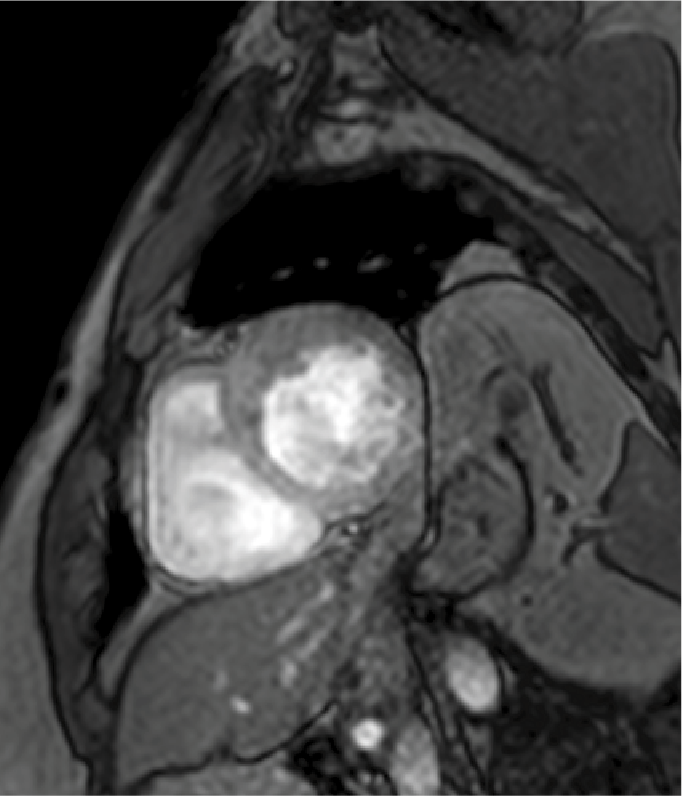

Resonancia magnética cardiaca

La resonancia magnética cardiaca es un una técnica de imagen que permite estudiar detalladamente y en una sola exploración la función y la estructura del corazón. Este auxiliar diagnóstico utiliza un potente campo magnético, sin radiación, para generar imágenes detalladas de las estructuras del corazón.

La resonancia magnética esta indicada en la evaluación de las cardiopatías congénitas tanto en el niño como en el adulto, en la evaluación de la perfusión miocárdica (resonancia cardiaca con gadolinio), de la función cardiaca, de las enfermedades del músculo cardiaco (miocardiopatías), tumores del corazón y del tejido que rodea al corazón (pericardio).